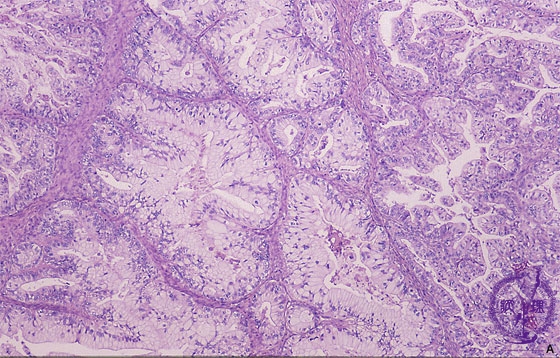

- (7)Mucinous cystadenocarcinoma of the ovary

Histology (HE stain, intermediate power): Carcinoma cells proliferated in tubular structure with producing abundant mucin.